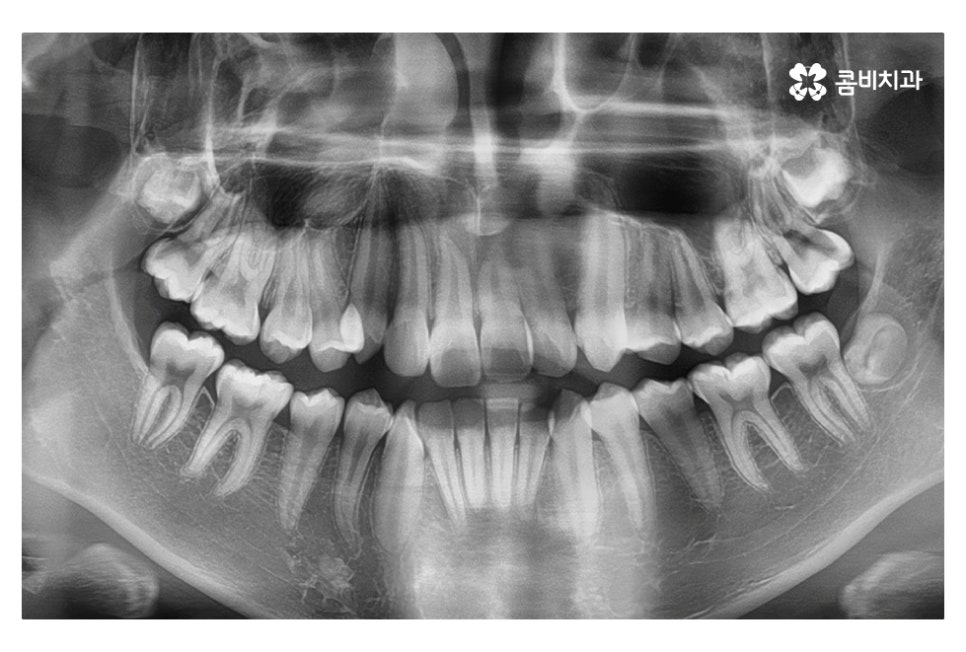

보이지 않는 부분까지 정확하게 진단하기 위해서는

3D CT 혹은 모르페우스와 같이 첨단 장비를 활용하는 것도

중요한 부분이라고 할 수 있어요.